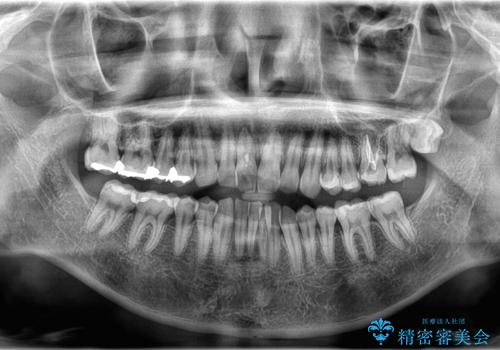

- 「上の前歯の捻じれと下の前歯のでこぼこを治したい」を主訴に来院された患者様です。

矯正検査の結果、非抜歯で矯正可能だったためインビザラインで治療を行いました。

アーチの拡大とIPRで叢生を改善いました。